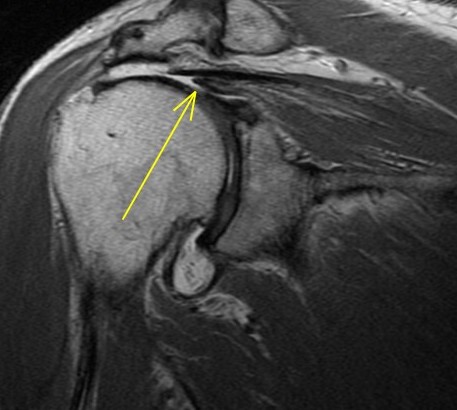

67 y/o with shoulder pain. Shoulder OA. R/O rotator Cuff tear.

The rotator cable is a collagenous thickening of the supraspinatus tendon which acts as a suspension bridge type mechanism strengthening its attachment. In my experience you dont see it in each case but in this case you see it well. Many supraspinatus tears involve the anterior aspect of the tendon and if severe enough can involve the cable and subscapularis tendon. Some consider it extending through the cable to involve the subscap. Biomechanically involvement of the cable can lead to weakness of supraspinatus function whereas if not involved the tear is said be “cresentic” and the patients usually have preserved strength – albeit are in pain. See the enclosed article. Reference article.

Supraspinatus and subscapularis tears involving the anterior rotator cable